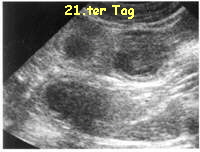

Ab dem 21. Tag kann man eine Ultraschalluntersuchung beim Tierarzt machen. Ab diesem Tag kann man auf dem Ultraschallbild etwas erkennen. Davon eine trächtige Fähe zu Röntgen um Welpen zu erkennen möchten wir abraten. Wir haben davon gehört, dass diese Methode auch benutzt wird. Die Ultraschalluntersuchung ist bestimmt nicht so bequem für den Halter und den Tierarzt, weil die Fähe dabei auch zappelt und man sie länger festhalten muss aber um einiges gesünder als das Röntgenbild.21.ter Tag

Bei der Untersuchung kann man feststellen ob alles soweit in Ordnung ist und ungefähr abschätzen wieviele Welpen die Fähe erwartet. Auf dem Ultraschallbild oben kann man 3 Fruchtkugeln also spätere Welpen erkennen. Das ist natürlich nur ein Ausschnitt, von diesem Bild kann man nicht auf die Anzahl der Welpen schliessen.